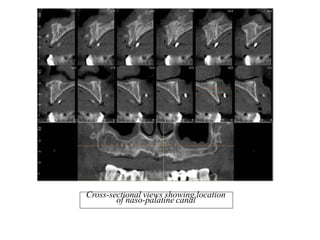

Nasopalatine canal on a

CBCT Coronal section

Cross-sectional views showing location

of naso-palatine canal